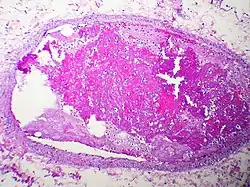

This pulmonary thromboembolism was the result of a thrombus (blood clot) detaching from the wall of a distant blood vessel. It then traveled through circulation until lodging in this pulmonary vessel, becoming a thromboembolism.